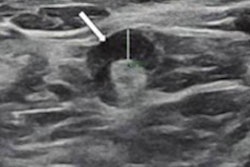

Ultrasound images of a 43-year-old asymptomatic woman without breast cancer show unilateral left axillary adenopathy after mRNA COVID-19 vaccination. (A) Images of the left axilla show enlarged lymph nodes with the cortex measuring up to 7.7 mm within the first week of BNT162b2 vaccination. (B.) Follow-up ultrasound images within six weeks (B) and (C) 12 weeks show decreased axillary lymphadenopathy of variable degrees, with the cortex measuring up to 5.7 and 3.4 mm, respectively. Image courtesy of the RSNA.After these women were vaccinated, persistent lymphadenopathy was observed in 25 women (51%). They found that complete resolution was observed at a median of six weeks, with a range of four to seven weeks, after vaccination in 23 women.